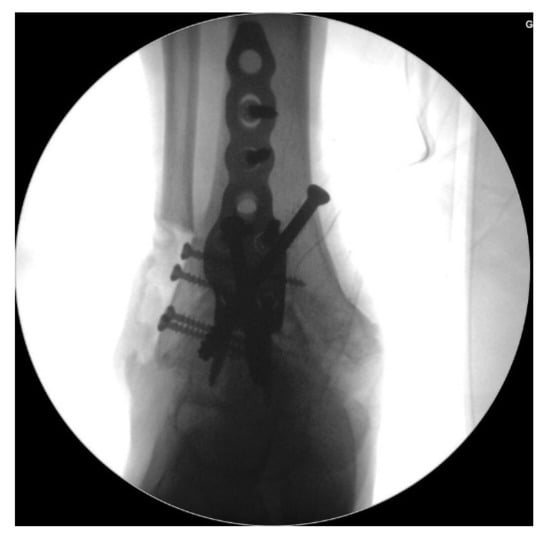

Surgery was performed with the patient in the lateral decubitus position, and it was possible to change to the supine position during the anterior approach. All patients received prophylactic antibiotics before surgery. An 8 to 10 cm lateral incision was made along the posterior border of the lateral malleolus to obtain a sufficient distance from the anterior incision (Figure 2). Soft tissue dissection was performed between the periosteum and the distal fibula to preserve the blood supply of the soft tissue. After exposure of the distal fibula, the fibula was transected 4 to 5 cm proximal to the ankle joint (Figure 3). The cartilage and subchondral bone of the tibiotalar joint were removed using curettes, osteotomes, and burrs through the lateral ankle joint (Figure 4). Following joint preparation, an anterior longitudinal incision of 6 to 8 cm was made by keeping a distance of 7 cm from the lateral incision. After dissection was performed between the tibialis anterior and extensor hallucis longus tendons to expose the joint, cartilage and subchondral bone of the medial gutter were removed (Figure 5). While the tibiotalar joint was being prepared, the resected fibular fragment was hemisected in the sagittal plane for use as a bone graft (Figure 6). The medial half was used as the filler of the arthrodesis site, and the lateral half was used as a lateral strut. The tibiotalar joint was reduced in a neutral and plantigrade position and temporarily fixed using a 2.4 mm-Steinmann pin. Subsequently, the arthrodesis site was fixed using the first 6.5-mm partially threaded cannulated screw from the posterior malleolus along the longitudinal axis of the talar neck and into the talar head as a homerun screw. The second 6.5-mm cannulated screw was placed from the metaphyseal flare of the medial distal tibia into the medial talar body. After screw fixation, additional anterior plating was performed using a 3.5-mm T-plate (Synthes, Paoli, PA, USA) in 29 ankles and an anatomical anterior fusion plate (Arthrex Inc., Naples, FL, USA) in 7 ankles through anterior incision (Figure 7). The lateral half of the resected fibula was fixed by four cancellous screws in its original anatomical position as a natural lateral bony plate (Figure 8). Reduction state and screw positioning without penetration of the subtalar joints were confirmed via fluoroscopy (Figure 9). The extensor retinaculum was meticulously closed with 2-0 absorbable sutures, followed by subcutaneous closure with 3-0 absorbable suture. The skin was closed with 4-0 monofilament sutures using the modified Allgöwer–Donati technique. Short leg casts were applied for 4 weeks following surgery. At 2 weeks after surgery, partial weight-bearing was started with crutches. Full weight-bearing with and without an ankle orthosis was allowed at 4 weeks and 8 weeks after surgery, respectively.

Figure 9. Reduction state and screw positioning without penetration of the subtalar joints were confirmed via fluoroscopy.